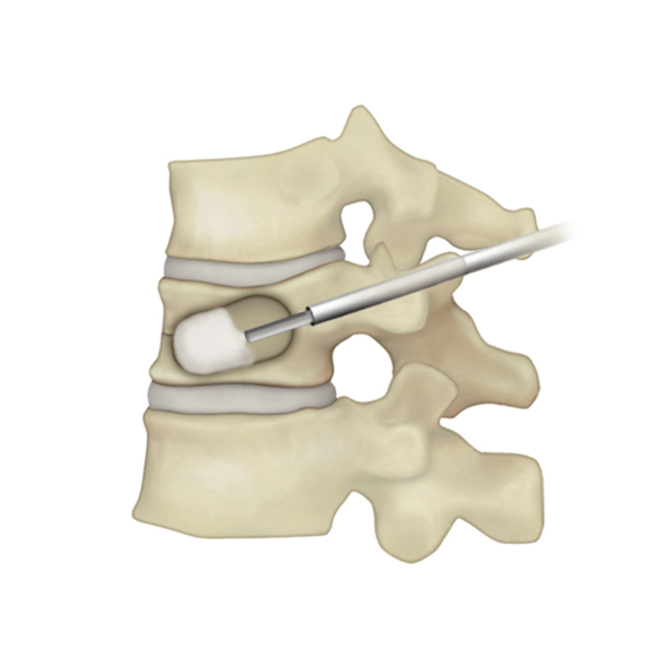

BKP治療手術の流れ

| 1)背中から針を刺入し骨折した椎体への経路を作成。小さな風船の付いた器具を挿入。 | 2)風船を徐々に膨らませつぶれた骨を持ち上げ骨折前の形に戻す。 | 3)風船を抜いて、その空間に骨セメントを充填する。 | 4)手術は約1時間程度。セメントは手術中に固まる。 |